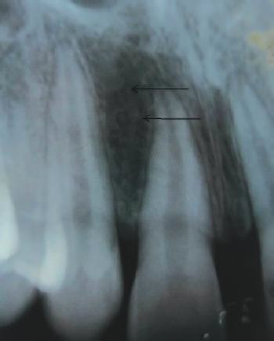

58. What is showing by arrow?

Inferior Alveolar Canal appears as a dark linear shadow with thin radiopaque superior and inferior borders cast by the lamella of bone that bounds the canal.